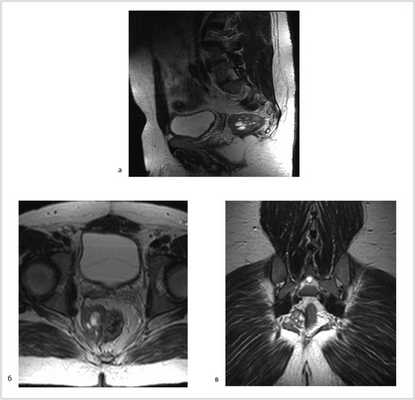

Рис. 3. МР-томограммы малого таза. Опухоль уменьшилась в размере до 5,5×3,5×4 см, однако тесно прилежит к правой стенке прямой кишки. а — аксиальный срез; б — сагиттальный срез; в — фронтальный срез.

В отделении проведен повторный консилиум с участием химиотерапевтов саркомной группы, хирургов сакральной группы, а также сотрудников отделения онкопроктологии. Учитывая нерадикальность предыдущей операции по поводу неэпителиальной опухоли малого таза, положительную динамику на фоне полихимиотерапии в виде уменьшения размера опухоли (более чем в два раза), а также молодой возраст пациента, принято решение вторым этапом выполнить оперативное вмешательство в объеме цилиндрической (экстралеваторной) брюшно-промежностной экстирпации прямой кишки, предложенной австрийским хирургом Т. Holm в 2007 г.

07.11.2012 выполнена цилиндрическая или экстралеваторная экстирпация прямой кишки. Через тазовую брюшину в мезоректальной клетчатке справа пальпируется верхний полюс опухоли, подрастающей к стенке прямой кишки, опухоль фиксирована к правой боковой стенке таза. Отдаленных метастазов нет (рис. 4).

Рис. 4. Этап операции. Ревизия опухоли.

Произведена мобилизация прямой кишки по левой и задней полуокружности, а также пресакрально до мышц тазового дна с соблюдением всех онкологических правил (рис. 5). По левой боковой стенке таза опухолевая капсула интимно прилежит к внутренней подвздошной вене и артерии, острым путем последняя мобилизована от магистральных сосудов.

Рис. 5. Этапы операции. а — мобилизация слева; б — мобилизация справа.

Далее сигмовидная кишка пересечена на уровне ее дистальной трети, а прямая кишка погружена в малый таз, при этом тазовая брюшина ушита над заглушенной культей прямой кишки. Затем сигмовидная кишка забрюшинно выведена в левом боковом отделе живота на переднюю брюшную стенку и сформирована плоская колостома, после чего брюшная полость ушита наглухо послойно (рис. 6).

Рис. 6. Этапы операции. а — ушивание тазовой брюшины; б — сигмостома.

Далее больной перевернут на живот в положении по типу «перочинного ножа» (рис. 7).

Рис. 7. Положение больного на столе (а). Вид операционного поля промежности (б).

После обработки операционного поля мобилизация прямой кишки продолжена из широкого промежностного доступа. Выполнено ушивание заднего прохода кисетным швом, намечены края резекции. В проекции крестцово-копчикового сочленения кожа и подкожная жировая клетчатка рассечены до задней крестцово-копчиковой связки. Последняя пересечена в поперечном направлении. Выполнена ампутация копчика с последовательным пересечением передней крестцово-копчиковой и крестцово-прямокишечной связок (рис. 8).

Рис. 8. Этапы операции. а — ушивание ануса; б — рассечение кожи и подкожной жировой клетчатки; в — пересечение крестцово-копчиковых связок.

Далее прямая кишка с опухолью в едином блоке мобилизована острым путем от предстательной железы и правой стенки таза, после чего выполнена цилиндрическая брюшно-промежностная экстирпация прямой кишки. Малый таз дренирован двумя силиконовыми дренажами и ушит наглухо (рис. 9).

Рис. 9. Этапы операции. а — мобилизация простаты; б — дренирование малого таза; в — конечный вид раны.